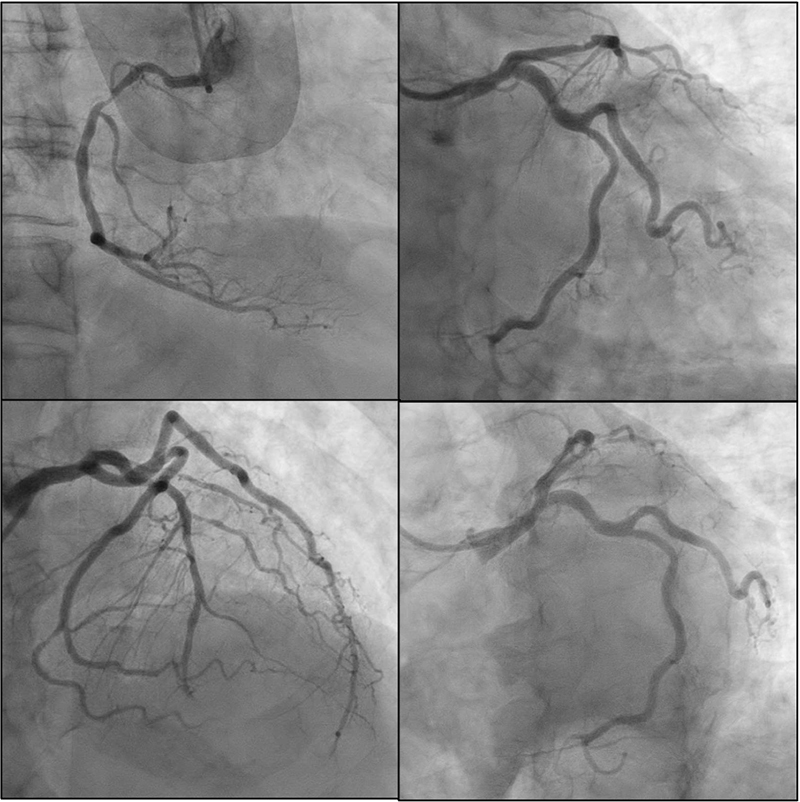

Emergent coronary angiography was performed via radial access. It revealed obstructive coronary artery disease (CAD) with 70% stenosis in the proximal left anterior descending artery (LAD), along with diffuse distal disease, and 80% stenosis in the proximal-to-mid segment of the right coronary artery (RCA) (Figure 2). The distal left main (LM) coronary artery showed 40–50% stenosis; however, intravascular ultrasound (IVUS) demonstrated a minimum luminal area of 7.8 mm2 with 43.1% stenosis (Figure 3). No unstable lesions were identified by intravascular imaging. Percutaneous intervention (PCI) was performed on the LAD using a 3.5 × 18 mm Xience drug-eluting stent (DES), with persistent TIMI-1 flow. The RCA underwent balloon angioplasty with a 2.5 × 20 mm compliant balloon, followed by placement of three Xience DES: 3.5 × 28 mm, 4 × 18 mm, and 3.5 × 8 mm.

Figure 2

Figure 2. Coronary angiogram. Obstructive CAD with 70% stenosis in the proximal LAD, along with diffuse distal disease, 80% stenosis in the proximal-to-mid segment of the RCA, and 40–50% stenosis of distal LM.